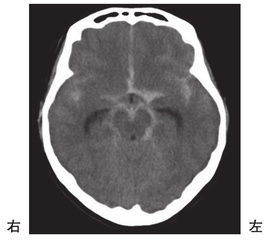

第54回 午前 作業療法士実地問題

科目:

頭部MRIのT2強調像を示す。正常圧水頭症の状態を示すのはどれか。

_n_O9RiVWwk78yruHnReI

1

2

3

4

5